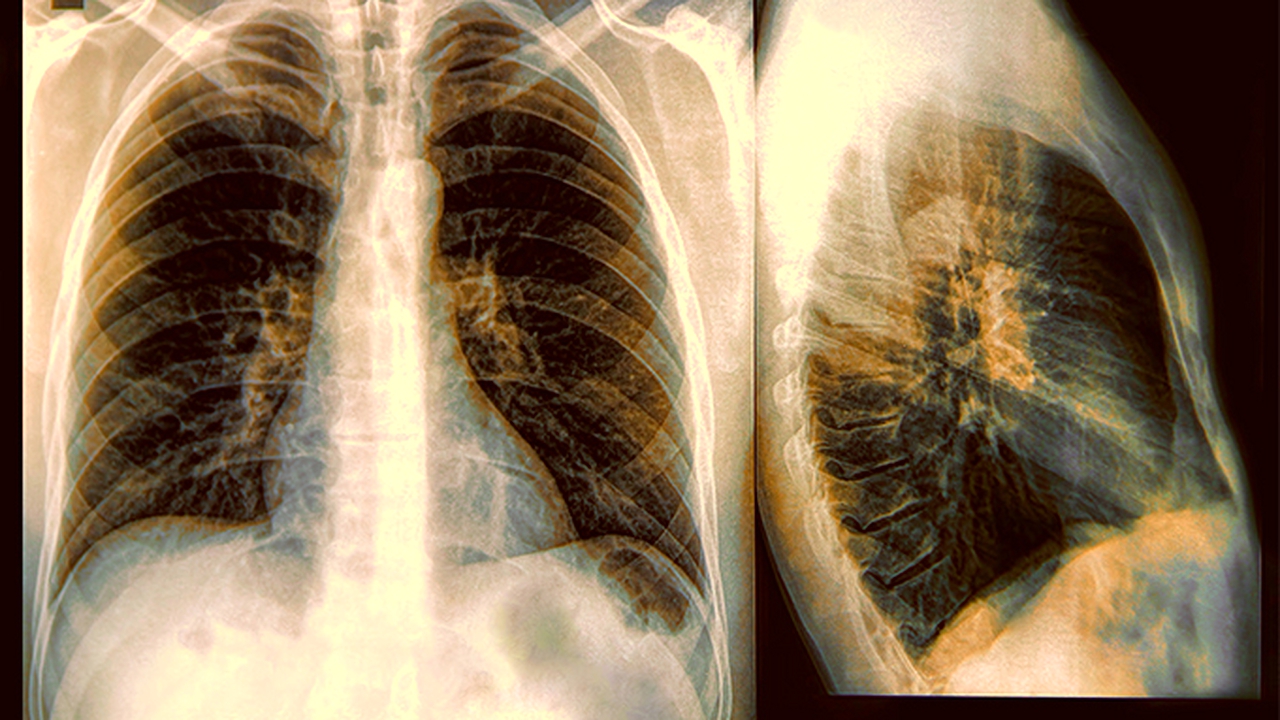

肺癌的发病原因复杂,长期吸烟、空气污染、职业暴露(如石棉、砷等)、遗传因素等均可能增加患病风险。早期诊断和规范治疗对提高生存率至关重要。

肺癌预防需重视戒烟和避免二手烟暴露,建议40岁以上长期吸烟者每年进行低剂量CT筛查。日常生活中应减少厨房油烟吸入,从事高危职业者需做好防护。确诊患者应保持均衡营养,适当进行呼吸功能锻炼,定期随访监测病情变化。医疗机构应加强肺癌防治科普,提高公众早筛意识。